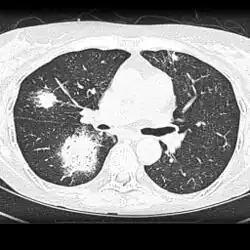

| Chest X-ray: widespread rounded lung nodules throughout both lungs | |

The extent of infection may be seen on X-ray or CT scan. On chest X-ray and CT, pulmonary aspergillosis classically manifests as a halo sign, and later, an air crescent sign.[21]

CT scan lungs: multiple lung lesions with ground-glass opacity suggesting haemorrhage